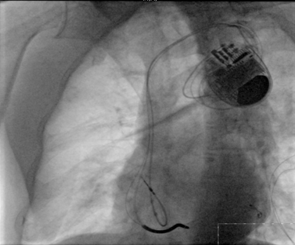

冠狀靜脈逆行造影

?“它的技術難點在于左室電極的植入”。朱彬介紹,除了常規(guī)的由于心臟擴大變形所致的冠狀靜脈竇口位置改變,自身冠狀靜脈解剖異常等問題外,傳統(tǒng)的左室電極安置后存在起搏位點選擇性小,起搏時容易出現(xiàn)膈神經(jīng)或膈肌刺激、起搏高閾值、為保證穩(wěn)定性將電極植入心尖而出現(xiàn)心尖部起搏,為避免心尖部起搏避開心尖位置但卻出現(xiàn)電極不穩(wěn)定術后移位等諸多問題。而左室四極電極導線由于可以有多個起搏位點和多種起搏向量的選擇,可一次性解決上述難題,能做到“電極植入心尖,起搏心底”。綜合患者具體情況,為提高手術成功率,降低手術風險,朱彬決定在該手術中使用目前國內最新型的左室四極電極。